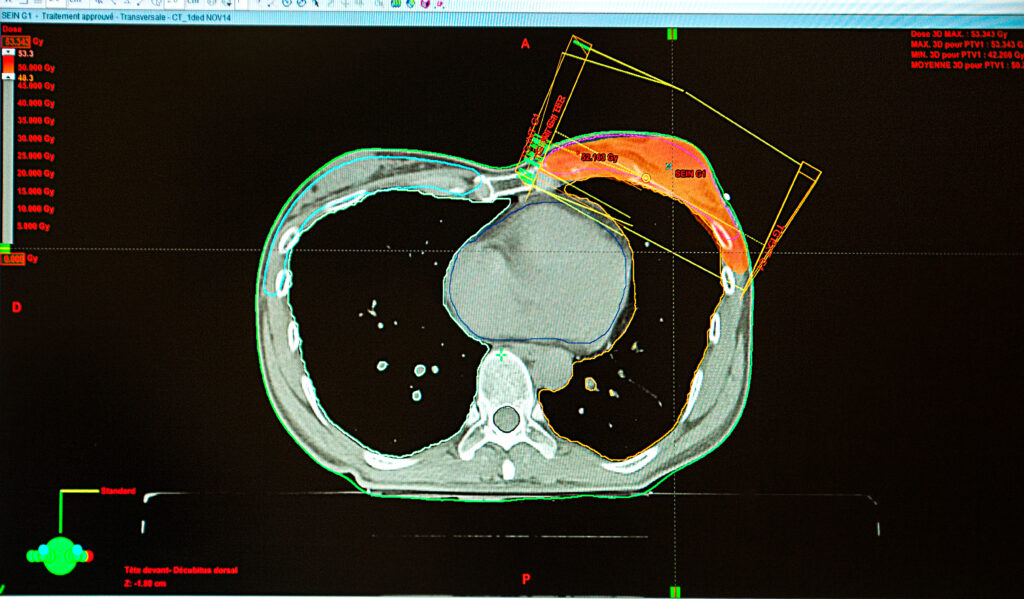

8 Must-Know Facts About the BioZorb Recall Posted: January 23, 2025 1. BioZorb Tissue Markers Are Used in Breast Cancer Treatment.In recent years, medical advancements have brought groundbreaking tools to improve patient care. Not all innovations succeed as planned. Hologic’s BioZorb tissue marker, a device used in breast cancer treatment, is a warning example. BioZorb is a device used in breast cancer treatment. It has been linked to serious complications. This has led to a recall and raised legal and health concerns for patients affected. Here’s what you need to know about the device, its recall, and your options if you’ve been impacted.Read More 2. What Is BioZorb and How Does It Work?BioZorb is a bio-absorbable implant designed to mark the site of a breast cancer tumor after surgical removal. Shaped like a small coil, the device contains titanium clips embedded in a polylactic acid (PLA) framework. It is intended to help doctors visualize and target the area for radiation therapy or future imaging. Over time, the PLA material is supposed to dissolve naturally in the body, leaving only the titanium clips behind.BioZorb has caused problems for many patients. This has led to serious health issues and a recall.Read More 3. Why Was BioZorb Recalled?Hologic issued a recall of the BioZorb tissue marker after reports surfaced of adverse effects, including:* Chronic pain and inflammation at the implantation site.* Infections that required antibiotic treatment or surgical removal of the device.* Migration of the implant, leading to complications in surrounding tissues.* Difficulty in removal, which posed additional risks during follow-up surgeries.The recall was classified as Class II by the FDA, meaning the device posed a health risk that could be mitigated with corrective action but was not deemed immediately life-threatening.Read More 4. FDA Sent a Warning Letter to Hologic.In a warning letter issued to Hologic, the U.S. Food and Drug Administration (FDA) cited concerns over the manufacturing processes for BioZorb. The letter noted:* Deficiencies in quality control measures.* Failure to properly report adverse events associated with the device.* Non-compliance with regulatory standards designed to ensure patient safety.The FDA’s warning underscored the serious nature of the problems linked to BioZorb, emphasizing that Hologic’s actions fell short of the safeguards required for medical devices.Read More 5. A Court Rejected Hologic’s Motion for Summary Judgment.On January 3, 2025, an important legal event took place. A judge denied Hologic’s request for summary judgment in lawsuits about BioZorb. This ruling allows claims from plaintiffs to move forward, signaling that the court found sufficient evidence to question whether Hologic adequately warned patients and healthcare providers about the risks of the device.For affected patients, this development strengthens the possibility of holding the manufacturer accountable for harm caused by BioZorb. The decision may lead to more examination of Hologic’s actions. It could also result in settlements or verdicts for the plaintiffs.Read More 6. Research Highlights BioZorb Problems.Several studies have raised red flags about BioZorb’s performance and safety profile. Research published in medical journals has documented:* Cases where the PLA framework failed to dissolve as expected, causing persistent pain and complications.* Evidence of inflammatory responses triggered by the implant’s materials.* Difficulties in imaging due to the migration or degradation of the device.These findings have led doctors to wonder if BioZorb’s benefits are worth the risks. This is especially true since there are other tissue markers that have fewer complications.Read More 7. What to Do If You Have a Recalled BioZorb ImplantIf you or a loved one has received a BioZorb implant, here’s what you should consider:* Consult Your Doctor Right Away: Talk to your healthcare provider to see if the implant is causing problems or risks to your health. Imaging studies or other diagnostic tests may be necessary.* Monitor for Symptoms: Be vigilant about signs of infection, pain, or unusual changes near the implant site. Early detection of complications can help prevent more serious issues.* Consider Removal: If the implant is causing harm or presents risks, your doctor may recommend removing it. Be sure to discuss the potential risks and benefits of such a procedure.* Document Everything: Keep records of your medical treatments, communications with healthcare providers, and any adverse effects you’ve experienced. This documentation can be crucial if you decide to pursue legal action.* Seek Legal Advice: Consider consulting an attorney who specializes in medical device litigation. They can help you understand your rights. They will evaluate your case. They can also see if you may get compensation for medical expenses, pain, suffering, or other damages.Read More 8. Patients Have the Right to Know the Risks of a Medical Device.The BioZorb recall has sparked a broader conversation about the safety and oversight of medical devices. Critics argue that regulatory agencies need to strengthen post-market surveillance to identify and address problems more quickly. Patients and healthcare providers, meanwhile, are calling for greater transparency from manufacturers about the risks associated with their products.The issues surrounding BioZorb also highlight the importance of informed consent. Patients have the right to know the possible benefits of a medical device. They should also understand the risks and uncertainties that come with it. When patients are fully informed, healthcare providers can help them make choices that focus on their safety and well-being.Read More BioZorb, Mass Torts News, Medical Device News What a Recent Lancet Retraction Means for the Talc Debate March 26, 2026 No Comments … Read More Meta and YouTube Found Negligent in Landmark Social Media Addiction Case March 25, 2026 No Comments … Read More Investor Alert: Investment Concerns Involving Mario Joseph Payne and Raymond James Financial Services March 11, 2026 No Comments … Read More NEC Baby Formula Litigation Grows as Reckitt Benckiser Explores Sale of Mead Johnson Nutrition Division March 6, 2026 No Comments … Read More Creative Planning LLC: What Investors Need to Know February 26, 2026 No Comments … Read More LP Attorney Cameron Stephenson Appointed to Plaintiffs’ Executive Committee in GLP-1 Vision Loss MDL February 24, 2026 No Comments … Read More Free Case Evaluation LinkedInThis field is for validation purposes and should be left unchanged.Name First Name Last Name Email(Required) Phone Number(Required)Describe your legal issueCommunications Consent I agree to LP's Policies and Disclaimers, and I consent to receive emails, calls, and texts, including those made by an automated system, from or on behalf of Levin Papantonio. My consent is effective even if my number is listed on any state, federal or corporate do-not-call registry. I understand my consent to receive automated marketing calls/texts is not required as a condition of purchasing any services and that I can revoke my consent, at any time, by writing to contact@levinlaw.com.I Understand and Agree(Required) I Understand and Agree Translate »